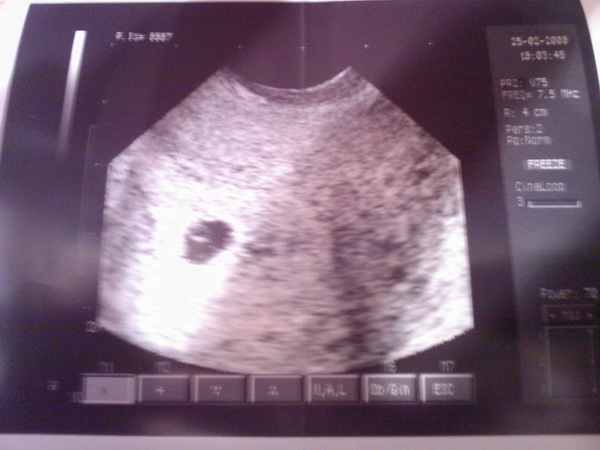

Én tegnap voltam dokinál. Minden rendben, egy baba van, jó helyen, korának megfelelő és jó vastag anyálkahártya, így bízunk benne, hogy jól be tudja fészkelni magát. Legközelebb két hét mulva kell majd mennem. Péntektől táppénzen vagyok, mert a doki ezt tanácsolta, én pedig megfogadom. Már szóltam is a munkahelyemen és remélem megértőek lesznek.

Teszek fel nektek képet a kicsi csigámról, aki még tényleg ici-pici :lol: Kép